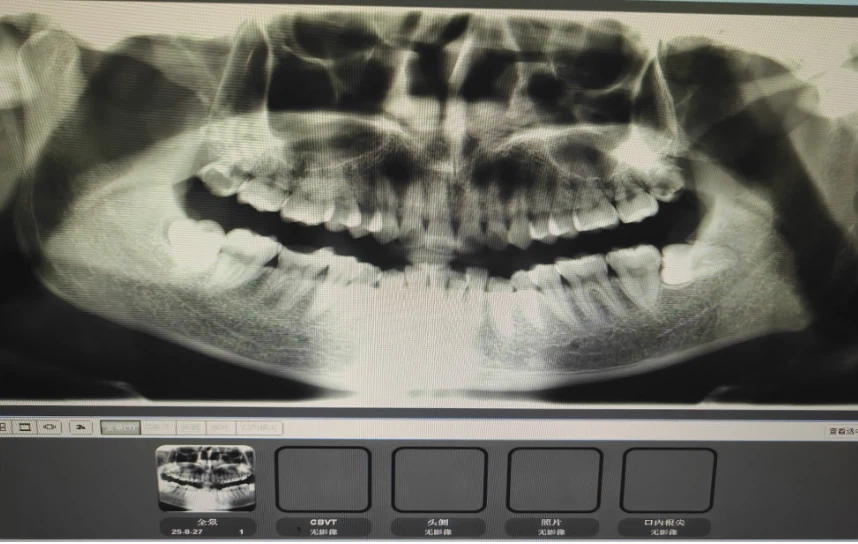

这期间我吃了各种药,比如阿莫西林,甲硝唑等等,效果都不是特别的好。有一天我实在痛的受不了了,就去了诊所找医生给我看一下,医生给我拍了片子,告诉我左下角这个智齿是横着长的,属于阻生牙,这颗牙一直往上长顶着我的一颗好牙,我看了一下片子,的确是这样,这时我意识到了,我这颗智齿可能是保不住了。决定去我们这省会城市的三甲医院拔牙。

找到给我看病的梁医生,梁医生也是很仔细的问了我病史,我把我在手机上拍照下来的在诊所拍的片子给他看,他看了一会儿告诉我这个牙齿很不好拔,而且拔了一定会肿,我表示知情。他还说了拔牙后可能导致的并发症(比如面神经麻痹,拔一半断在里面等等),虽然听起来很吓人,但是我也是医生知道这种概率很小,于是果断的在知情同意书上签了字。最后医生还说我上面的智齿也有问题,建议我一起拔掉,我犹豫了一会儿还是只拔这颗痛的,下次要是发作我再来拔(后来证明我是对的)。交完费后,我躺在了治疗床上,拔牙就正式开始了。